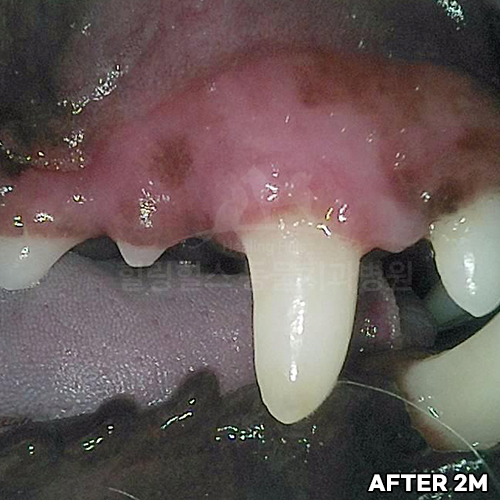

[치주치료 후 자기잇몸뼈 재생!!]

[치주염 치료 후 자라난 잇몸뼈]